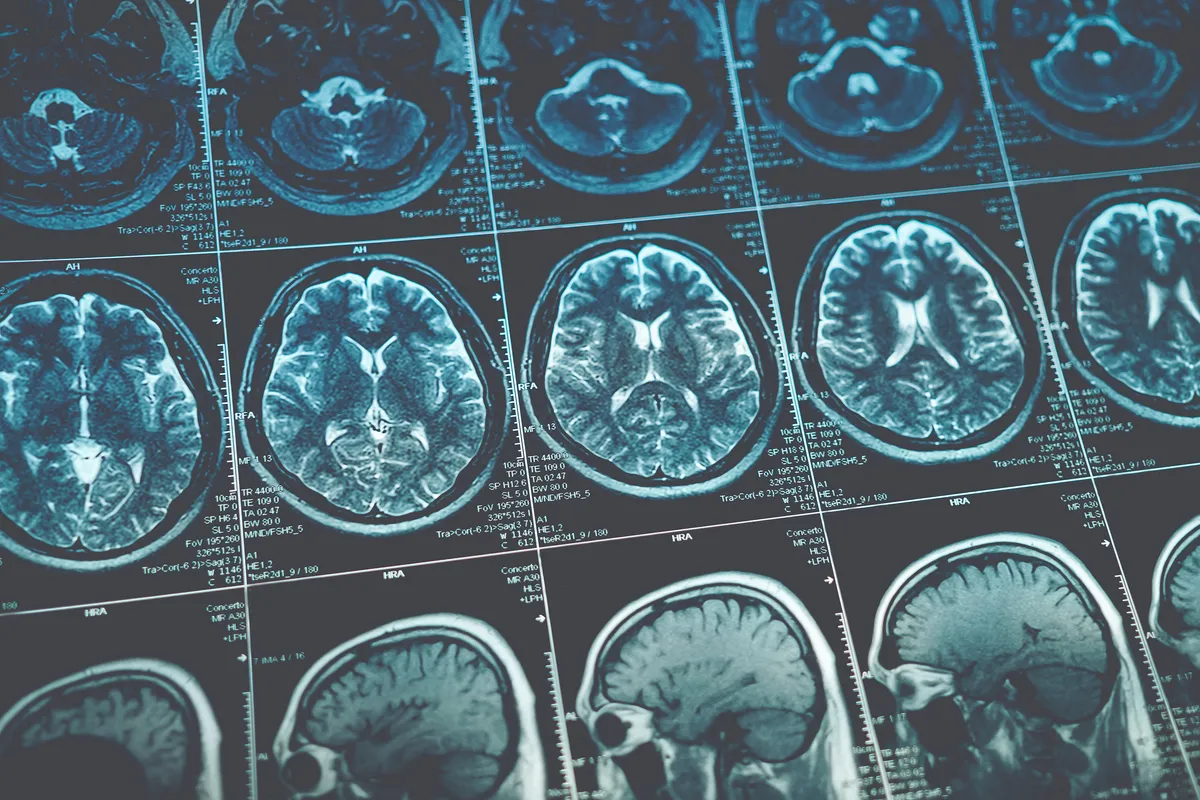

Більшість наших дій контролюється скоординованим зв’язком між нейронами в різних ділянках мозку. Нейробіологи можуть отримати уявлення про те, як ділянки мозку організовують складні функції, спостерігаючи за нейронною активністю у стані спокою за допомогою функціональної магнітно-резонансної томографії (фМРТ).

Дані, отримані за допомогою rs-fMRI, є безцінними для вчених, які вивчають цілий ряд неврологічних розладів і станів. Порівнюючи результати сканування людей з такими станами, як, наприклад, СДУГ, з результатами сканування нейротипових людей, ми сподіваємося, що зможемо виявити закономірності, які можуть пояснити деякі особливості цих станів.